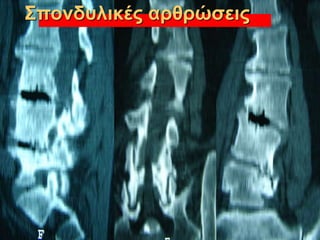

Πηγές πόνου

Μεσοσπονδύλιοι δίσκοι

Σπονδυλικές αρθρώσεις

Πλευροσπονδυλικές αρθρώσεις

Αστάθεια